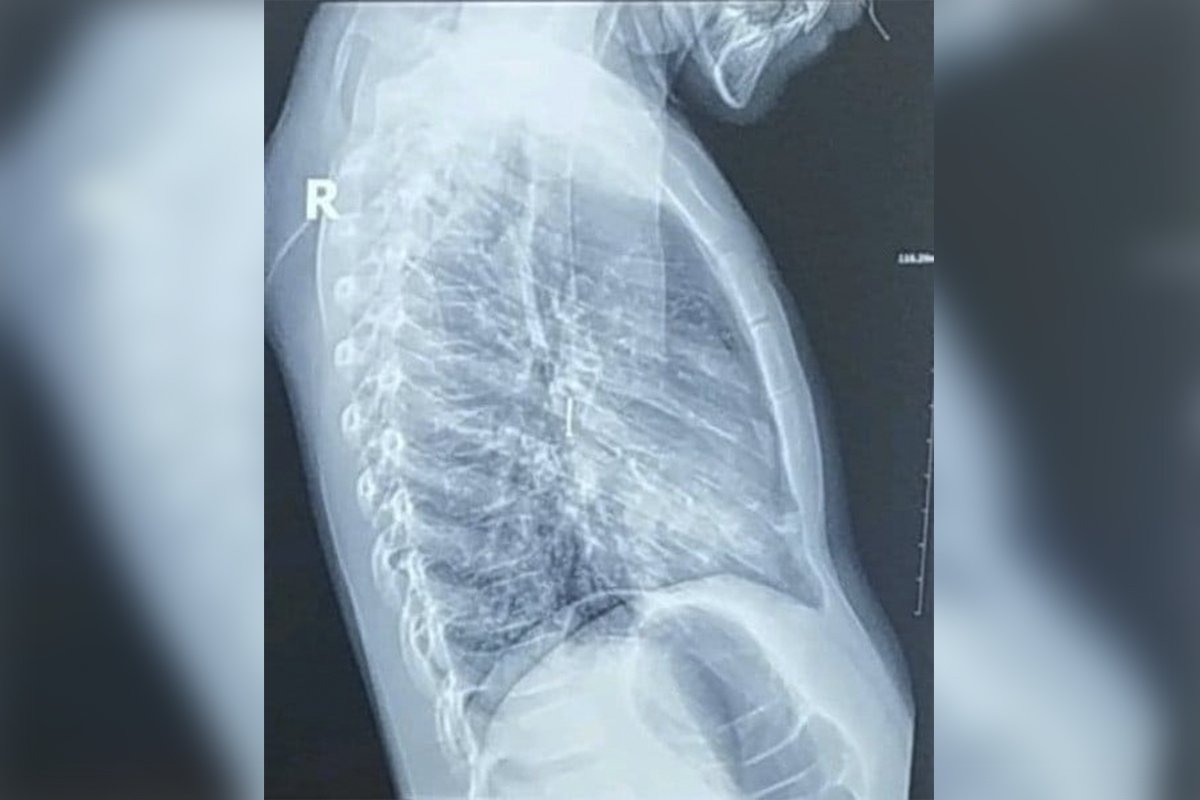

В Днепре родители 7-летнего ребенка обратились к семейному врачу с жалобами на кашель. Во время рентгена специалисты обнаружили в бронхах постороннее тело.

Как оказалось, ребенок вдохнул канцелярскую кнопку, и она попала в правый бронх. Об этом сообщает Информатор, ссылаясь на публикацию врача-эндоскописта Сергея Щудро. Ребенку провели ригидную бронхоскопию, а на третьи сутки выписали домой, сейчас с ним все в порядке.